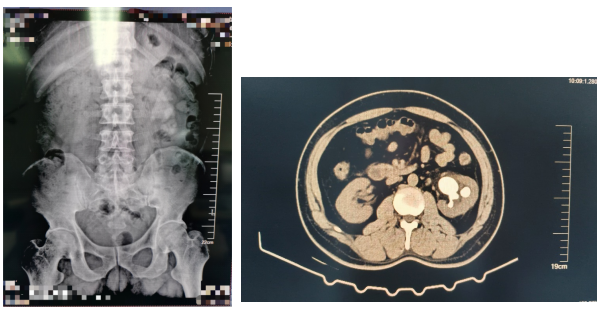

患者,男,46岁,主因左侧腰腹部间断性疼痛10天。于我院查泌尿系CT示左肾鹿角状结石、右肾结石收入院。后在可控负压吸引下行输尿管软镜钬激光碎石术治疗肾结石。

术前视图如下: